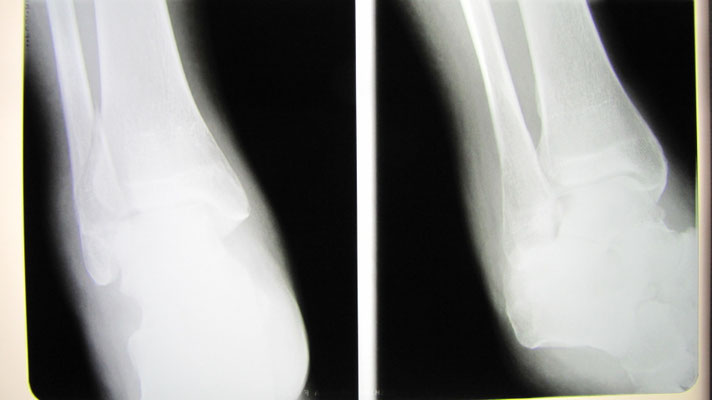

●左腓骨遠位端骨折

足首を捻り外側の骨 足首に近いところを骨折をしてしまいました。整形外科での診断後 手術の予定が決まりそれまでの間シーネ固定することになりましたが、手術療法に不安があり保存療法(自然療法)をインターネットで検索中当院のホームページにたどりつきました。

実は患者さんは他府県に住まれていたので近隣の他の整形外科でセカンドオピニオンを得ることを提案しましたが、どこの先生方も手術療法をすすめました。

結果的に2時間以上かけて当院に来院。保存療法で治療することになりました。コンパクトな固定ギプスと患部の血行を促進 超音波治療により腫れも痛みも軽減。経過良好でした。

4か月後には予定していた巡礼の旅 50kmの道を完歩することができました。なによりも手術の痕を残さず自然療法で完治したことに喜んでもらえました。